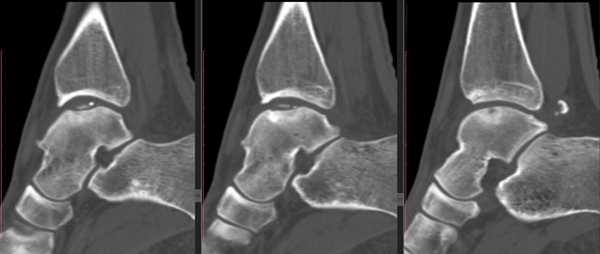

Не смотря на то, что Loomer с соавт. сообщили, что только от 50% до 66% остеохондральных дефектов обнаруживаются при помощи обычной рентгенографии, данный метод является важной отправной точкой и может быть полезен для исключения другой патологии голеностопного сустава [20]. Рентгенологическое исследование голеностопного сустава должно включать переднюю, заднюю и в 3⁄4 внутренней ротации проекции. Все проекции выполняются стоя (под нагрузкой) и называются функциональными. Функциональные рентгенограммы могут быть полезны для выявления сопутствующей нестабильности голеностопного сустава, проекция 3⁄4 во внутренней ротации, помогает в визуализации щели межберцового синдесмоза, а так же отображает передне-внутрений импижмент (таранной и большеберцовой кости) в случае его наличия. Выполненные в положении подошвенного сгибания прямая и 3⁄4 проекция во внутренней ротации могут быть полезны в выявлении заднемедиального поражения таранной кости. Рентгенологические признаки, которые могут быть определены, варьируются от небольших участков сдавления субхондральной кости до крупных отслоенных остеохондральных фрагментов. Радиографическая

система классификации была разработана Berndt и Harty в 1959 году и остается золотым стандартом. (Табл. 1) [16]. Loomer с соавторами дополнили имеющуюся классификацию, на основе не только рентгенограмм, а также МРТ (магнитно-резонансная томография) и КТ (компьютерная томография), и добавили стадию V в систему классификации Berndt и Harty [22].

МРТ является ценным инструментом в комплексе диагностики ОХПТК для оценки отека костной ткани, а также выявления скрытых повреждений субхондральной кости и хрящевого покрытия, которые могут быть пропущены при стандартных рентгенограммах или даже КТ. МРТ - самый лучший инструмент оценки для определения стабильности и жизнеспособности фрагмента таранной кости при его отслоении и эта информация может быть решающей в тактике выбора того или иного метода хирургического лечения. Однако, для определения размеров отслоившегося фрагмента таранной кости наилучший метод КТ, так как данные размеров по МРТ могут не соответствовать действительности в сторону переоценки последних. Hepple с соавторами изучив многочисленные данные МРТ диагностики разработали систему классификации ОХПТК на основе этого метода (Табл. 2) [23]. Однако, наиболее широко принятая система классификации, основанная на КТ-это классификация Ferkel и Sgalione (Табл. 3; Рисунок 4) [24]. Классифицировать ОХПТК также возможно выполнить интраоперационно, на основе артроскопических данных о состоянии остеохондрального поражения. Наиболее широко используется система Ferkel/Cheng (Табл. 4) [25], эта система классификации, в отличие от обычных рентгенограмм, КТ и МРТ, лучше всего взаимосвязана с исходами лечения пациентов.

На КТ определяется остеохондральное повреждение таранной кости.